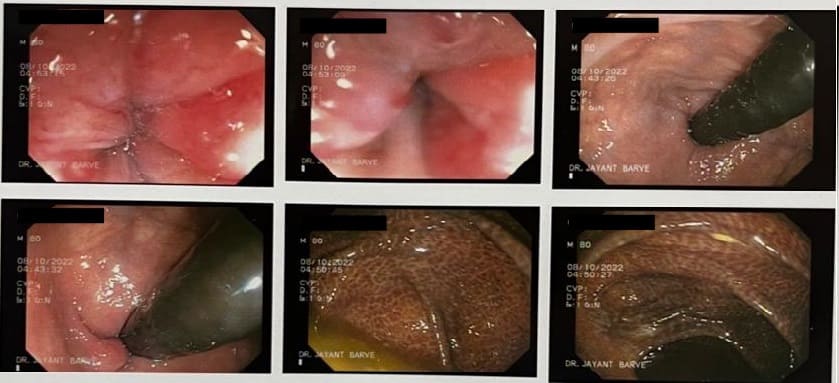

COLONOSCOPY

Colonoscopy is a procedure where the doctor can examine the lowermost part of the digestive tract

by a flexible instrument called as Colonoscope. Common indications for Colonoscopy are

7. Frank blood in the stool, occult blood in the stool or anaemia.

The correct diagnosis of cancer of the colon or rectum if made in time can offer a curative treatment.

Major bleeding in the stool in elderly people is commonly due to diverticulitis of colon.

This is a condition where there are balloon like projections arising from colonic mucosa and

which bleed due to rupture of a blood vessel. Colonic polyps is also an important condition to diagnose because

polyps have potential of becoming cancerous in future. Removal of polyp by polypectomy without

open surgery can offer cure in the early stage of cancer. A proper follow-up can keep the patient free from cancer.

Altered bowel habits, watery or semisolid stools, gripping pain in abdomen, mucus and blood in the stool,

incomplete evacuation can all be due to a condition called as colitis. Colitis has got different causes

like ulcerative colitis, Crohn’s disease, infections, tuberculosis, amoebic colitis, bacillary dysentery and many more.

Corrcet diagnosis by Colonoscopy will allow patients to be treated properly.